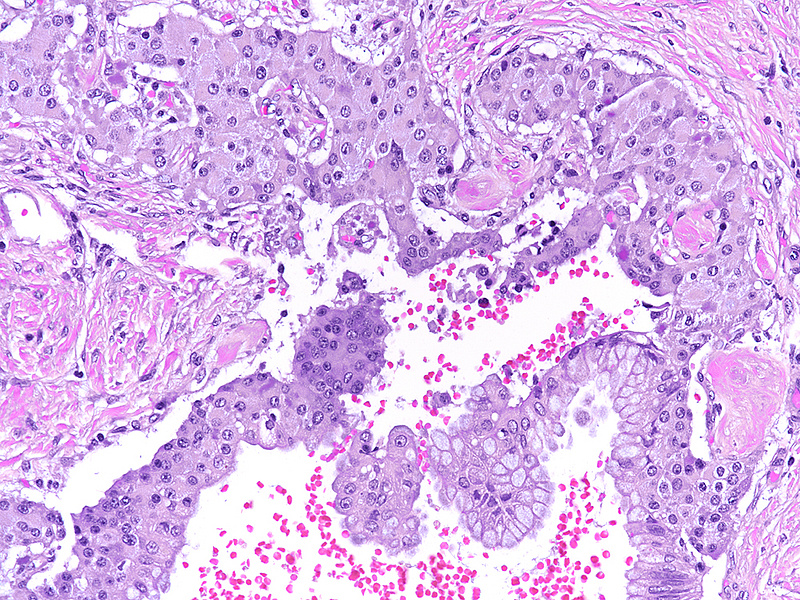

Upon magnetic resonance imaging (MRI) the pancreas contains several cystic lesions plus one partly solid, partly cystic lesion with a maximum diameter of 15 mm within the body. This lesion shows a biphasic pattern (Panel A). There are cysts lined by mucin-producing columnar cells with low grade dysplasia, consistent with a diagnosis of intraductal papillary mucinous neoplasm (IPMN). Other parts show a mainly solid, but also pseudoglandular growth of cuboidal cells with eosinophilic granular cytoplasm and centrally placed nuclei with “salt and pepper” chromatin and small nucleoli (Panels B-C). Mitoses are not detected. The two components merge with each other (Panel D), and in some foci the eosinophil granular cells underline the columnar cells (Panel E). The solid tumour component is strongly positive for synaptophysin (Panel F) and chromogranin A (Panel G), as are the underlining cells within the cystic component (Panel H). The Ki67 proliferation rate is low in the columnar epithelium (Panel I) and even lower (4%) in the solid component (Panel J). It is of note that the cells within the solid component express glucagon, while the cyst-lining mucus-producing cells are negative (Panels K-L).